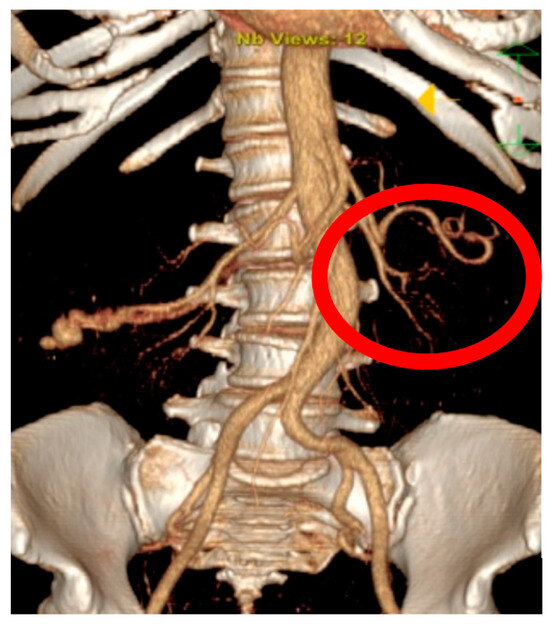

Appendix A.1. Clinical Case 1: Right Renal Visceral Arteriovenous Malformation